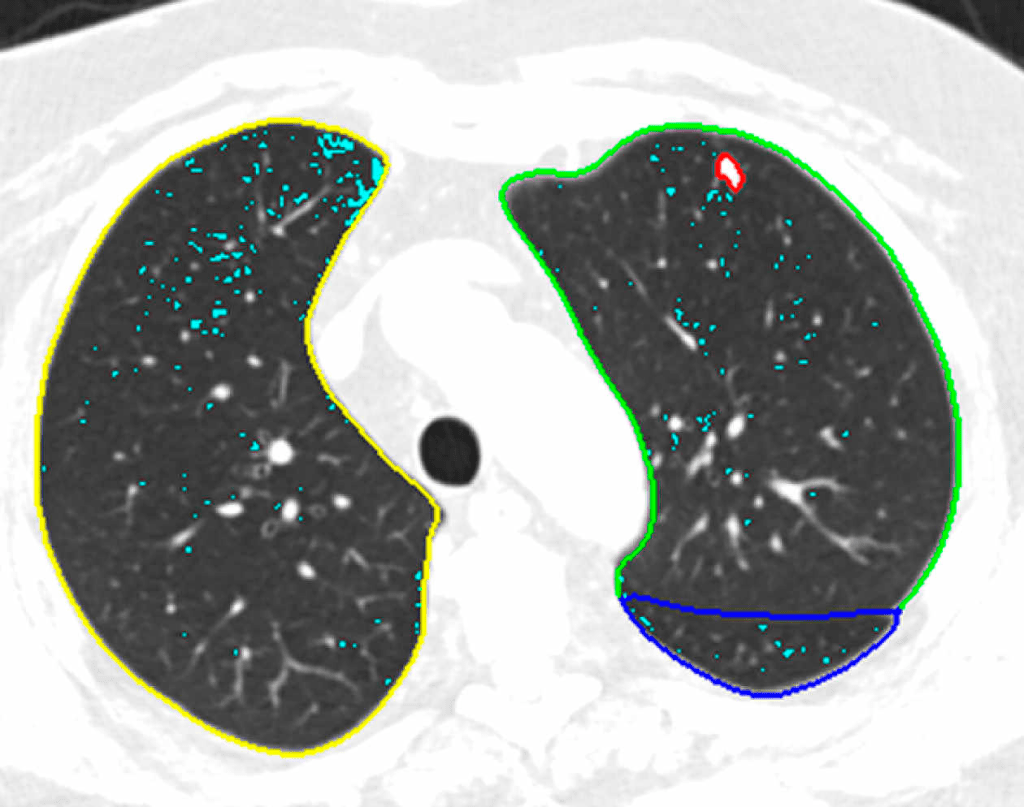

Détection de nodules pulmonaires cancéreux par l’IA au scanner, à l’hôpital Foch. HOPITAL FOCH

Cela n’empêche cependant pas l’hôpital de continuer sa politique volontariste. L’IA est utilisée pour dépister les nodules pulmonaires depuis 2021 et en mammographie depuis janvier 2022. Un logiciel pour détecter l’embolie pulmonaire est actuellement en évaluation. « Nous sommes sur la courbe dite “de Gardner” : toute révolution technologique connaît, dans son utilisation, une période d’euphorie, une pente de la désillusion, avant de trouver un niveau asymptotique correct d’utilisation. Nous sommes dans une certaine désillusion, mais cela va évoluer. Entre-temps, nous devons nous approprier ces outils, nous acculturer pour bien inclure cette brique dans le work flow [“flux de travail”] », affirme-t-il.

Alors que « beaucoup de solutions d’IA sont proposées sans performances cliniques validées en France », continue Isabelle Thomassin, une initiative, Drim France IA, a été lancée par le Conseil national professionnel de la radiologie (qui rassemble radiologues libéraux, universitaires, hospitaliers et sociétés savantes) afin de clarifier la situation et d’aider les radiologues à s’y retrouver. Cette association de loi 1901 a sollicité les start-up éditrices afin de « répondre à une grille analytique et descriptive de leurs solutions pour les aides au diagnostic de cancer du sein, de fractures osseuses et de nodules pulmonaires, qui constituent la majorité des logiciels proposés sur le marché français ». Des démarches similaires, portées respectivement par l’American College of Radiology et la Canadian Association of Radiologists sont en cours aux Etats-Unis et au Canada.